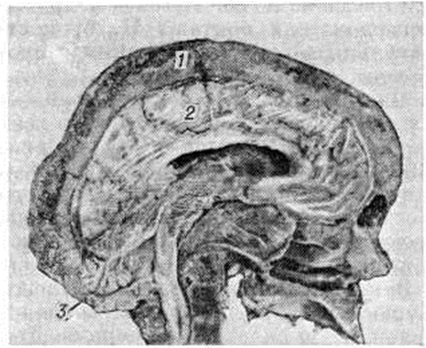

Педжета болезньПеджета болезнь (J. Paget, английский хирург и патолог, 1814—1899; синонимы: деформирующий остоз, деформирующий остит, фиброзная остеодистрофия, деформирующая остеодистрофия) — заболевание скелета диспластического характера с развитием патологической перестройки, что приводит к его характерной деформации. Заболевание впервые описал Дж. Педжет в 1877 год и назвал его osteitis deformans, считая, что в его основе лежит воспалительный процесс. Современники Педжета стали называть заболевание его именем. Позднее Педжета болезнь была объединена в одну группу с болезнью Реклингхаузена (смотри полный свод знаний: Паратиреоидная остеодистрофия) в связи с некоторым сходством гисто л. данных и получила название фиброзного остита. Штенхольм (Т. Stenholm, 1924) доказал дистрофический, а не воспалительный характер процесса при этих заболеваниях и предложил новое название — фиброзная остеодистрофия. К. Шморль (1930) выделил Педжета болезнь в самостоятельную группу и назвал её деформирующей остеодистрофией. А. В. Русаков и другие исследователи считают Педжета болезнь постнатальным диспластическим процессом. Частота Педжета болезнь составляет 0,1 — 3%. Заболевание встречается во всех странах света, чаще в Австралии, США, Западной Европе, реже в Китае, Японии, странах Ближнего Востока, Индии, Африке. Мужчины болеют чаще. Иногда Педжета болезнь возникает у нескольких членов семьи. Этиология точно не определена. Существует много гипотез: воспалительная, высказанная впервые Дж. Педжетом, гипотеза о врождённом пороке биосинтеза соединительной ткани кости, эндокринная, аутоиммунная, сосудистая, неопластическая, диспластическая. Перспективной считают вирусную гипотезу, так как обнаруживают вирусоподобные включения в ядрах остеокластов поражённой кости. Патогенез. Сущность процесса при Педжета болезнь обусловлена усиленной патологический перестройкой костной ткани, которая характеризуется многократно чередующейся сменой процессов резорбции кости и её новообразования, что приводит к своеобразной микроструктуре кости, названной К. Шморлем мозаичной. Этот процесс ведёт к понижению прочности костей и деформации их под влиянием нагрузки. В основе патогенеза при Педжета болезнь лежат глубокие нарушения метаболизма костной ткани, о чем говорят изменения некоторых биохимических констант крови и мочи больных (высокая активность щелочной фосфатазы, оксипролинурия). Патологическая анатомия. Изменения могут развиваться в одной или нескольких костях скелета (монооссальиая и полиоссальная формы), но никогда не бывают генерализованными в отличие от гиперпаратиреоидной остео дистрофии. Наиболее частая локализация процесса — таз, позвоночник, череп, бедренные и большеберцовые кости. Начальные проявления болезни морфологически почти не изучены. В поздний период становится заметным утолщение, искривление, обезображивание костей, нарушение их внутренней архитектоники. При поражении черепа процесс чаще начинается с лобной кости и распространяется на теменную, теменно-височную и затылочную области. Кости лицевого черепа поражаются сравнительно редко. Заболевание характеризуется возникновением на ограниченном участке кости очага из волокнистой остеогенной ткани и простейших, слабо обызвествленных губчатых структур. Постепенное увеличение зоны поражения приводит к утолщению, спонгиозированию костей, изменению величины и формы черепа (рисунок 1). Выраженность патологический изменений у разных больных неодинакова. Поверхность поражённого отдела кости красноватая, под периостом видны множественные мелкие отверстия сосудистых каналов. Рисунок кровеносных сосудов на внутренней поверхности костей черепа сохранен. Изменённая кость достигает 3—6 сантиметров толщины. На распиле видны поля остеосклероза (смотри полный свод знаний), участки разрежения костных структур, островки кроветворной и жировой ткани. В костях черепа преобладают однородные мелкоячеистые структуры, в большем количестве располагающиеся на внутренней костной пластинке (рисунок 2). Анатомо-топографические соотношения между костями черепа постепенно нарушаются. Передняя черепная ямка, скат основания черепа уплощаются (платибазия), боковые отделы средней ямки и задняя черепная ямка прогибаются, затылочная кость оседает на заднюю дугу атланта. |